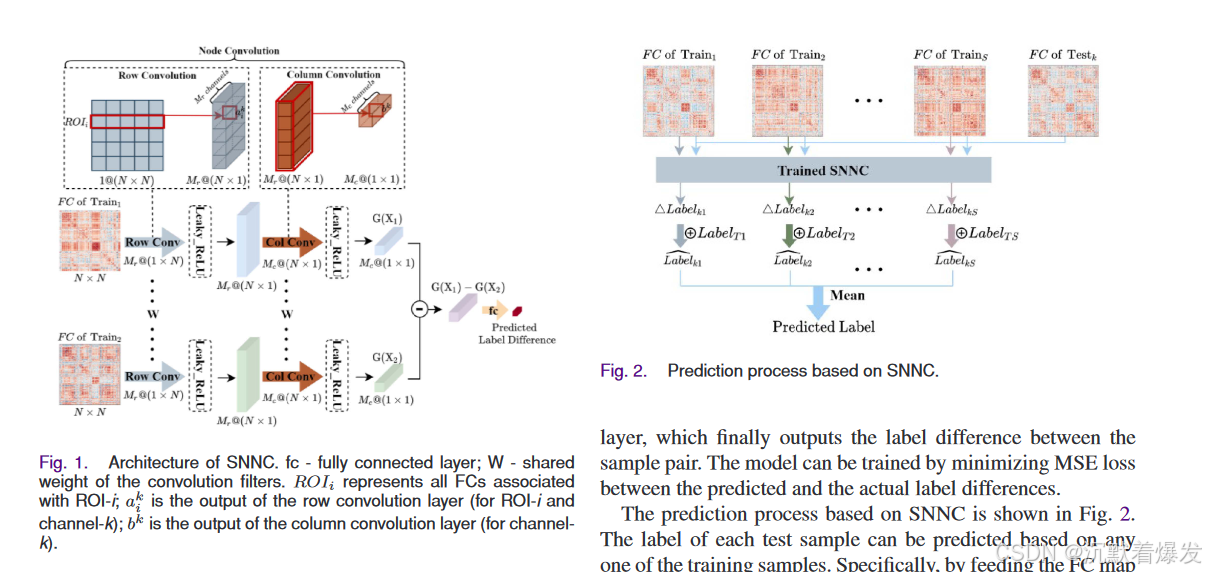

在本研究中,我们提出了一种基于静息态功能磁共振成像数据的具有节点卷积的Siamese网络( SNNC )用于(用途)个性化预测。(样本对作为输入的孪生网络解决样本量不足的问题)通过使用样本对(而不是单个样本)作为输入的孪生网络的参与,可以在很大程度上缓解样本量不足的问题。

**(具体做法)为了适应从静息态功能磁共振成像数据中提取的连通图,我们将节点卷积应用于Siamese网络的两个分支中的每个分支。为了回归的目的,我们将经典Siamese网络中的(论文创新点)**对比损失替换为均方误差损失,从而使Siamese网络能够定量地预测标签差异。测试样本的标签可以根据任何一个训练样本进行预测,方法是将训练样本的标签与它们之间的预测标签差值相加。本研究中测试样本的最终预测是通过平均每个训练样本的预测结果来实现的。

在这项研究中,我们提出了SNNC,一种基于静息态功能磁共振成像数据的节点卷积个性化预测的新型孪生网络。四个因素使SNNC成为基于静息态功能磁共振成像的个体化预测的有吸引力的选择。首先,节点卷积很好地适应了连通性图,并在促进后期预测方面表现良好;其次,Siamese架构在进行基于神经图像的预测分析时,很大程度上缓解了模型训练样本量不足的问题。第三,孪生网络学习样本对之间的标签差异,最终有利于定量预测。最后,基于SNNC的模型具有可解释性。SNNC不仅可以应用于静息态功能磁共振成像数据,还可以应用于其他可以提取连接图的神经影像学数据模态,如DTI、EEG、MEG等。

这里图1给出了基本的方法架构,图二是给出的预测过程,图画的很清晰很明了。

这里图1给出了基本的方法架构,图二是给出的预测过程,图画的很清晰很明了。